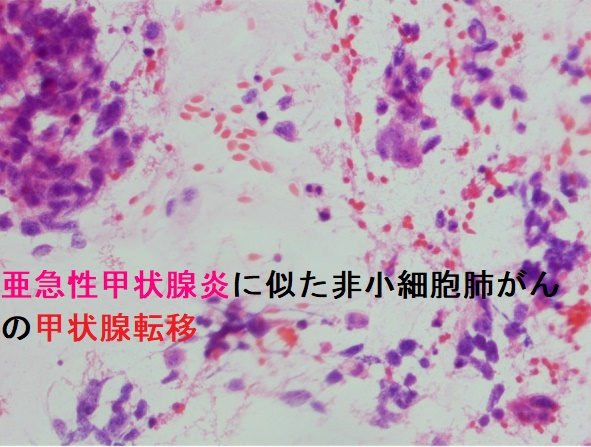

転移性甲状腺癌(他臓器癌から甲状腺へ転移)は①乳癌②肺癌(最多)③腎臓癌(臨床的に最も問題)④悪性黒色腫⑤胃がん・大腸がん・食道がんなど。超音波エコー検査で①低エコー領域②腺腫様甲状腺腫・良性濾胞腺腫・甲状腺濾胞癌と見分け付かず。癌性リンパ管炎をおこすと急激な前頚部腫脹、びまん性甲状腺腫、圧痛、破壊性甲状腺炎(甲状腺中毒症)、エコーで①びまん性低エコー像②樹枝状低エコー(拡張したリンパ管)③甲状腺腫大のみでSOL・低エコーを形成せず亜急性甲状腺炎・急性化膿性甲状腺炎と鑑別要。穿刺細胞診で低分化癌、未分化癌と判定され簡単に診断可能。

筆者の経験では、穿刺細胞診の報告書に「低分化癌」との病理診断が書いてある事が多く、確定診断には組織生検(コアニードル生検)が必要。[Otolaryngol Head Neck Surg. 2016 Apr;154(4):618-25.]

同様の報告として、肺腺癌術後の小寛解期に、急激な甲状腺腫大をおこし、甲状腺未分化癌が疑われるも穿刺細胞診で甲状腺低分化型乳頭癌の診断。、しかし、組織生検では腺癌細胞が乳頭状増殖しており、甲状腺低分化型乳頭癌に似ているが乳頭癌特有の核所見なし。

転移性甲状腺癌の穿刺細胞診所見は、

- 原発巣と同じ細胞が出れば確定

原発巣が腺癌では、腺腔形成、重積傾向の強い乳頭状集塊扁平上皮癌では、オレンジG好性細胞、紡錘形細胞の集塊

- 実際、腺腫様甲状腺腫、良性濾胞腺腫(淡明細胞型)、甲状腺濾胞癌などと鑑別できないことがある

特定できたとしても、低分化癌、未分化癌と言う結果で、臓器を特定できない、あるいは甲状腺原発かどうかも分からない事が多い

- 癌性リンパ管炎は、穿刺細胞診でしか診断不能。組織生検(コア生検)で確定

筆者の経験では、穿刺細胞診の病理診断結果は低分化癌として返ってくる事が多く、確定診断には組織生検(コアニードル生検)が必要

(同様の報告)肺腺癌術後、小寛解期に急激な甲状腺腫大をおこし、甲状腺未分化癌が疑われて穿刺細胞診すると甲状腺低分化型乳頭癌の病理診断。組織生検(コア生検)では、腺癌細胞が乳頭状増殖しているが、乳頭癌特有の核所見なし。